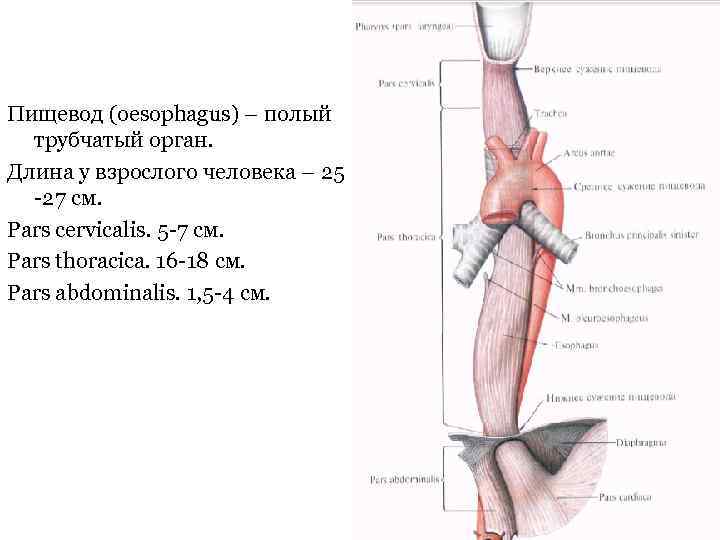

Пищевод (oesophagus) – полый трубчатый орган. Длина у взрослого человека – 25 -27 см. Pars cervicalis. 5 -7 см. Pars thoracica. 16 -18 см. Pars abdominalis. 1, 5 -4 см.

Пищевод (oesophagus) – полый трубчатый орган. Длина у взрослого человека – 25 -27 см. Pars cervicalis. 5 -7 см. Pars thoracica. 16 -18 см. Pars abdominalis. 1, 5 -4 см.

Скелетотопия пищевода. Начинается на уровне VI шейного позвонка и впадает в желудок на уровне XII грудного позвонка.

Скелетотопия пищевода. Начинается на уровне VI шейного позвонка и впадает в желудок на уровне XII грудного позвонка.